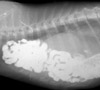

Lola, una gatita europea de unos 2 años llega al hospital con prediagnóstico de hernia diafragmática realizada meses atrás cuando fue encontrada y recogida en la calle por su dueña. Tras cuatro o cinco meses de convivencia y de ver como Lola respiraba penosamente al final se decidió a intervenirla quirúrgicamente. Las radiografías y fotos tomadas antes de la cirugía durante y poscirugía, enseñan el tremendo defecto diafragmático que hacía que prácticamente todo el contenido abdominal estuviese alojado en cavidad torácica lo que conllevaba esa disnea (dificultad respiratoria) tan severa en Lola. La sutura del defecto se realizó con material monofilamento no absorbible. Las fotos de Lola son del día siguiente a la intervención quirúrgica, día en que regresó a casa. La intervención ha sido un éxito y deseamos a Lola una larga y sana vida junto a su dueña.

El diagnóstico definitivo de mediante radiología o ecografía.